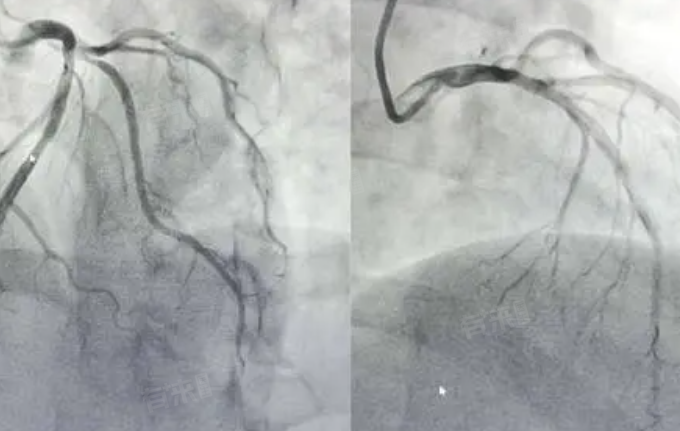

4、病情复杂程度:对于病情简单、心脏结构正常的患者,检查费用相对较低,大约在4500-6500元。但对于病情复杂,如存在多支血管病变、心脏畸形等情况的患者,由于需要更多的准备工作,费用可能在7000-10000元。